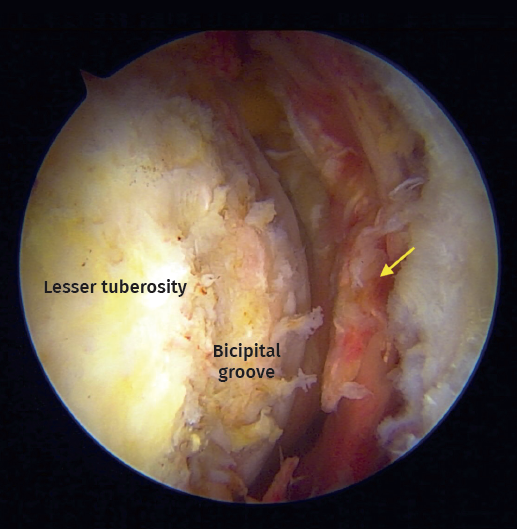

Figure 2. Arthroscopic view from anterolateral portal on a right shoulder in beach chair positioning. Chronic biceps tendon rupture. Arrow: Full-thickness and retraction of the subscapularis tendon